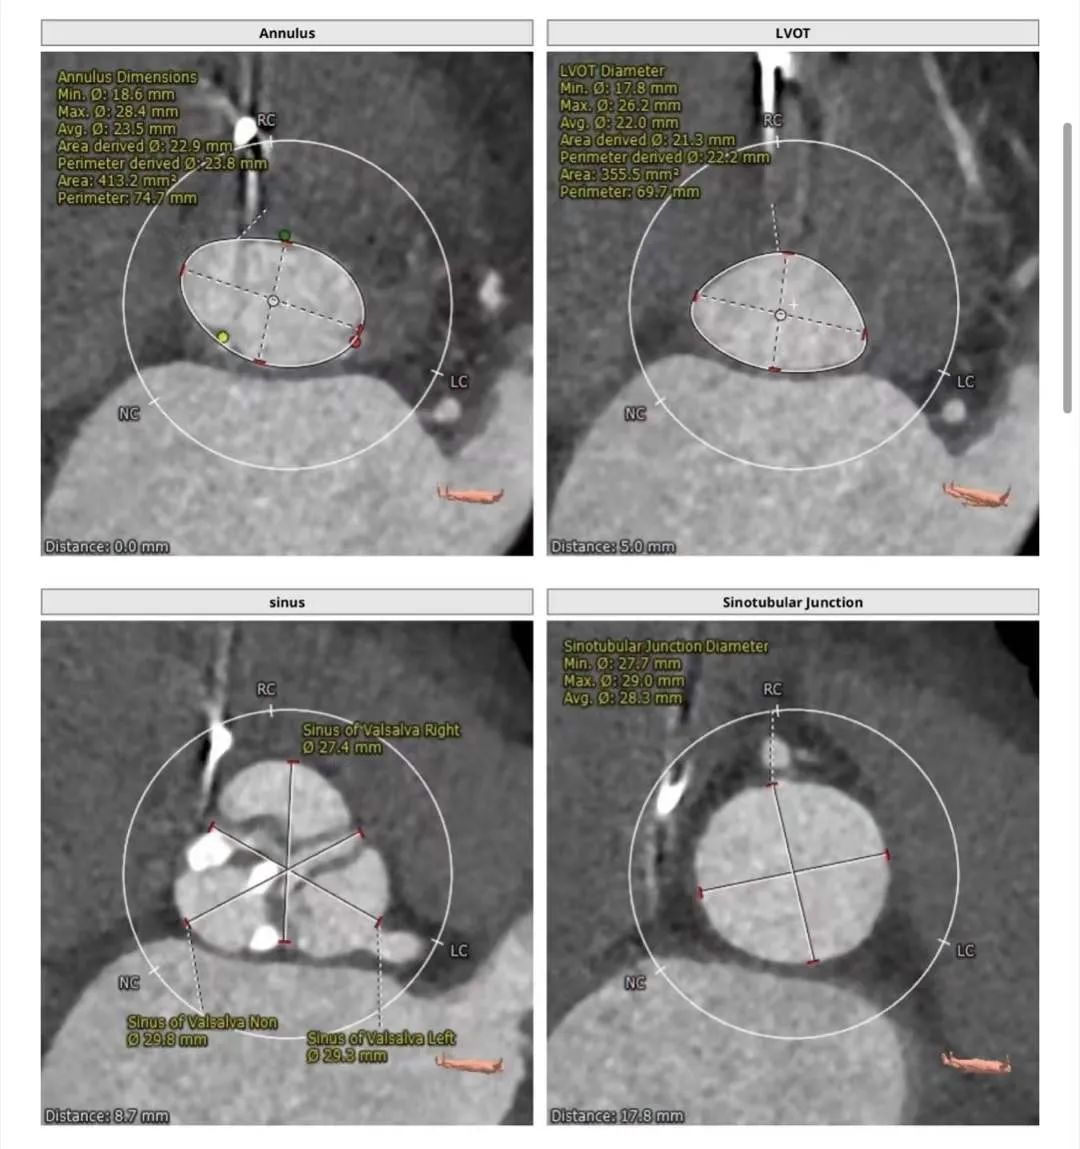

主动脉CT

难点分析:

患者为三叶瓣,中重度钙化,右冠高度可,但左冠高度8mm,且瓣叶达到冠脉开口上缘,法式窦结构不大,综合考虑冠脉风险高。